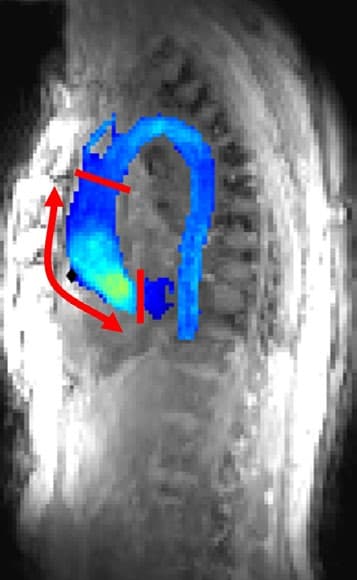

This study investigates the use of deep learning applied to wearable seismocardiography (SCG) signals for predicting aortic hemodynamics and diagnosing aortic valve stenosis. Using convolutional neural networks (CNN) and continuous wavelet transform (CWT) scalograms, the model achieved high correlation (r = 0.76) with peak systolic velocity (Vmax) values obtained via 4D flow MRI and classified valve conditions with ROC-AUC values ranging from 81% to 95%. The findings suggest SCG-based methods could serve as cost-effective alternatives or supplements to 4D flow MRI for screening and diagnosis of aortic valve diseases.